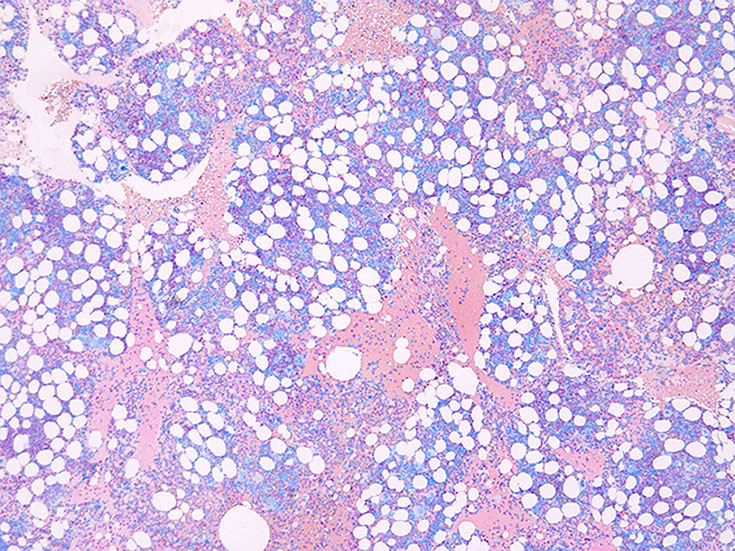

Panmyelosis--Bone marrow hypercellularity for age with trilineage growth

骨髄吸引クロット組織

cellularity 50-60%. 3系統造血細胞の増殖を認める. maturation arrestはない.

特に赤芽球系細胞が強く増殖している所見ではなく, 顆粒球系細胞増多がめだち, 巨核球の増加もある.

ETを含む慢性骨髄増殖性腫瘍 MPNの多くは, 多かれ少なかれ巨核球増多がみられ, CMLでも巨核球増多が見られる症例が多く, PVはより巨核球の増多が見られる.